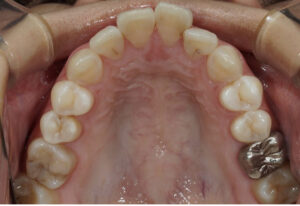

上

途中経過1年5ヶ月です。上